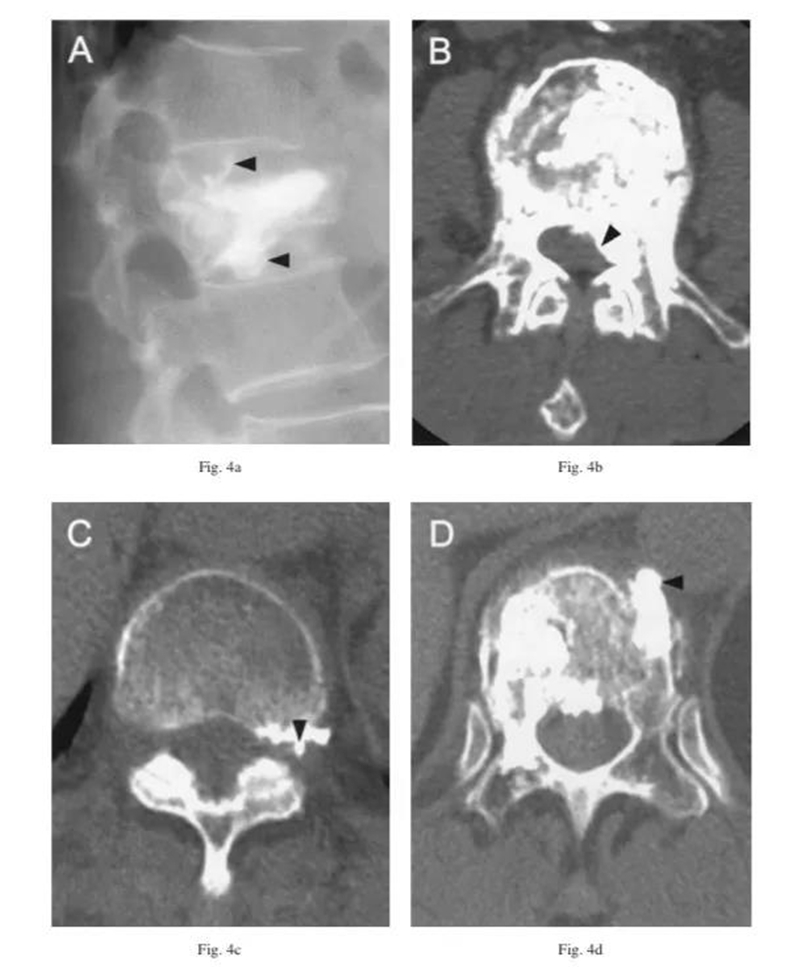

椎弓根外侧入路不走椎弓根,走椎旁。不伤神经,却有可能伤及椎旁节段血管。

该患者做完PVP术后失血性休克症状。复查CT发现巨大的腹膜后血肿。血管造影发现L2左侧节段动脉远端破裂,行栓塞修复。

三维CT显示椎旁节段动脉就在椎体旁正中走行,所以椎弓根外侧穿刺安全边界在椎弓根中线以上。